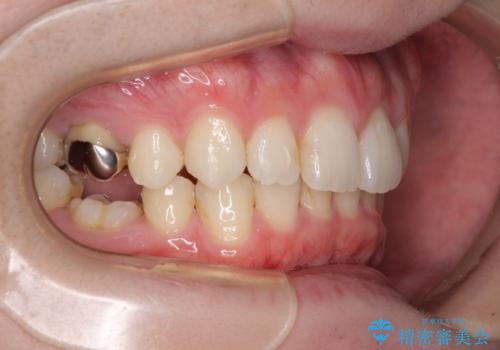

インビザラインによる矯正治療と奥歯のインプラント治療

- 咬み合わせと前歯のデコボコを気にして来院された患者様です。

前から5番目の永久歯が3本欠損しており、乳歯が残存している状態でしたが、インビザラインでも十分に対応可能と判断し、インビザラインにて矯正治療を行うこととしました。

右下の残存している乳歯は萌出しきれておらず、全く咬み合っていない状態であり、インビザラインにて移動できない可能性があるため、ワイヤー矯正の併用も念頭に置いて治療を開始しました。

今回は部分的にワイヤー矯正を用いましたが、右下の乳歯は全く動かなかったため、抜歯をした上でインプラントを埋入し、オールセラミッククラウンにて補綴治療を行いました。